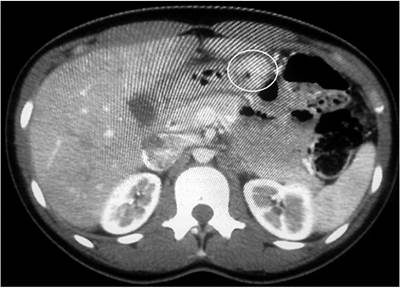

Se trata de un hombre de 35 años que consultó por un cuadro de dolor epigástrico de 6 meses de evolución, con una pobre modulación con analgésicos convencionales e inhibidores de la bomba de protones (IBP), asociado con episodios de lipotimia en varias oportunidades desde el inicio del cuadro y con antecedente de obesidad mórbida y apnea del sueño. Su examen físico estuvo dentro de límites normales. Se le realizó inicialmente una esofagogastroduodenoscopia y una tomografía axial computarizada (TAC), en las cuales se evidenció una lesión de aspecto tumoral de 2 cm a nivel de la cara posterior del antro (Figura 1). Posteriormente, se le solicitó biopsia por ultrasonografía endoscópica (USE), en la cual se evidenció una lesión subepitelial dependiente de la capa muscular que podría corresponder a un GIST.

Figura 1 Imagen por TAC en la que se evidencia, en la región antral, la presencia de una lesión sólida exofítica de contornos lobulados que capta el contraste, con un diámetro de 17 x 20 mm, y que podría estar relacionada con un tumor de GIST.